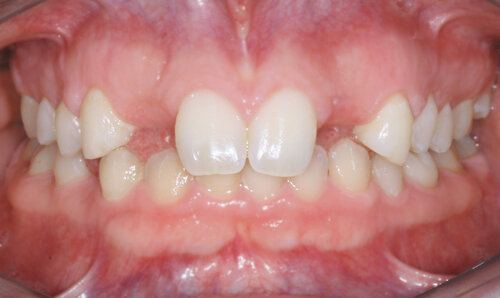

Intraoral imaging system at Beaverton Periodontics

After

The patient received a wonderful aesthetic and functional result with porcelain crowns over the implant fixtures.